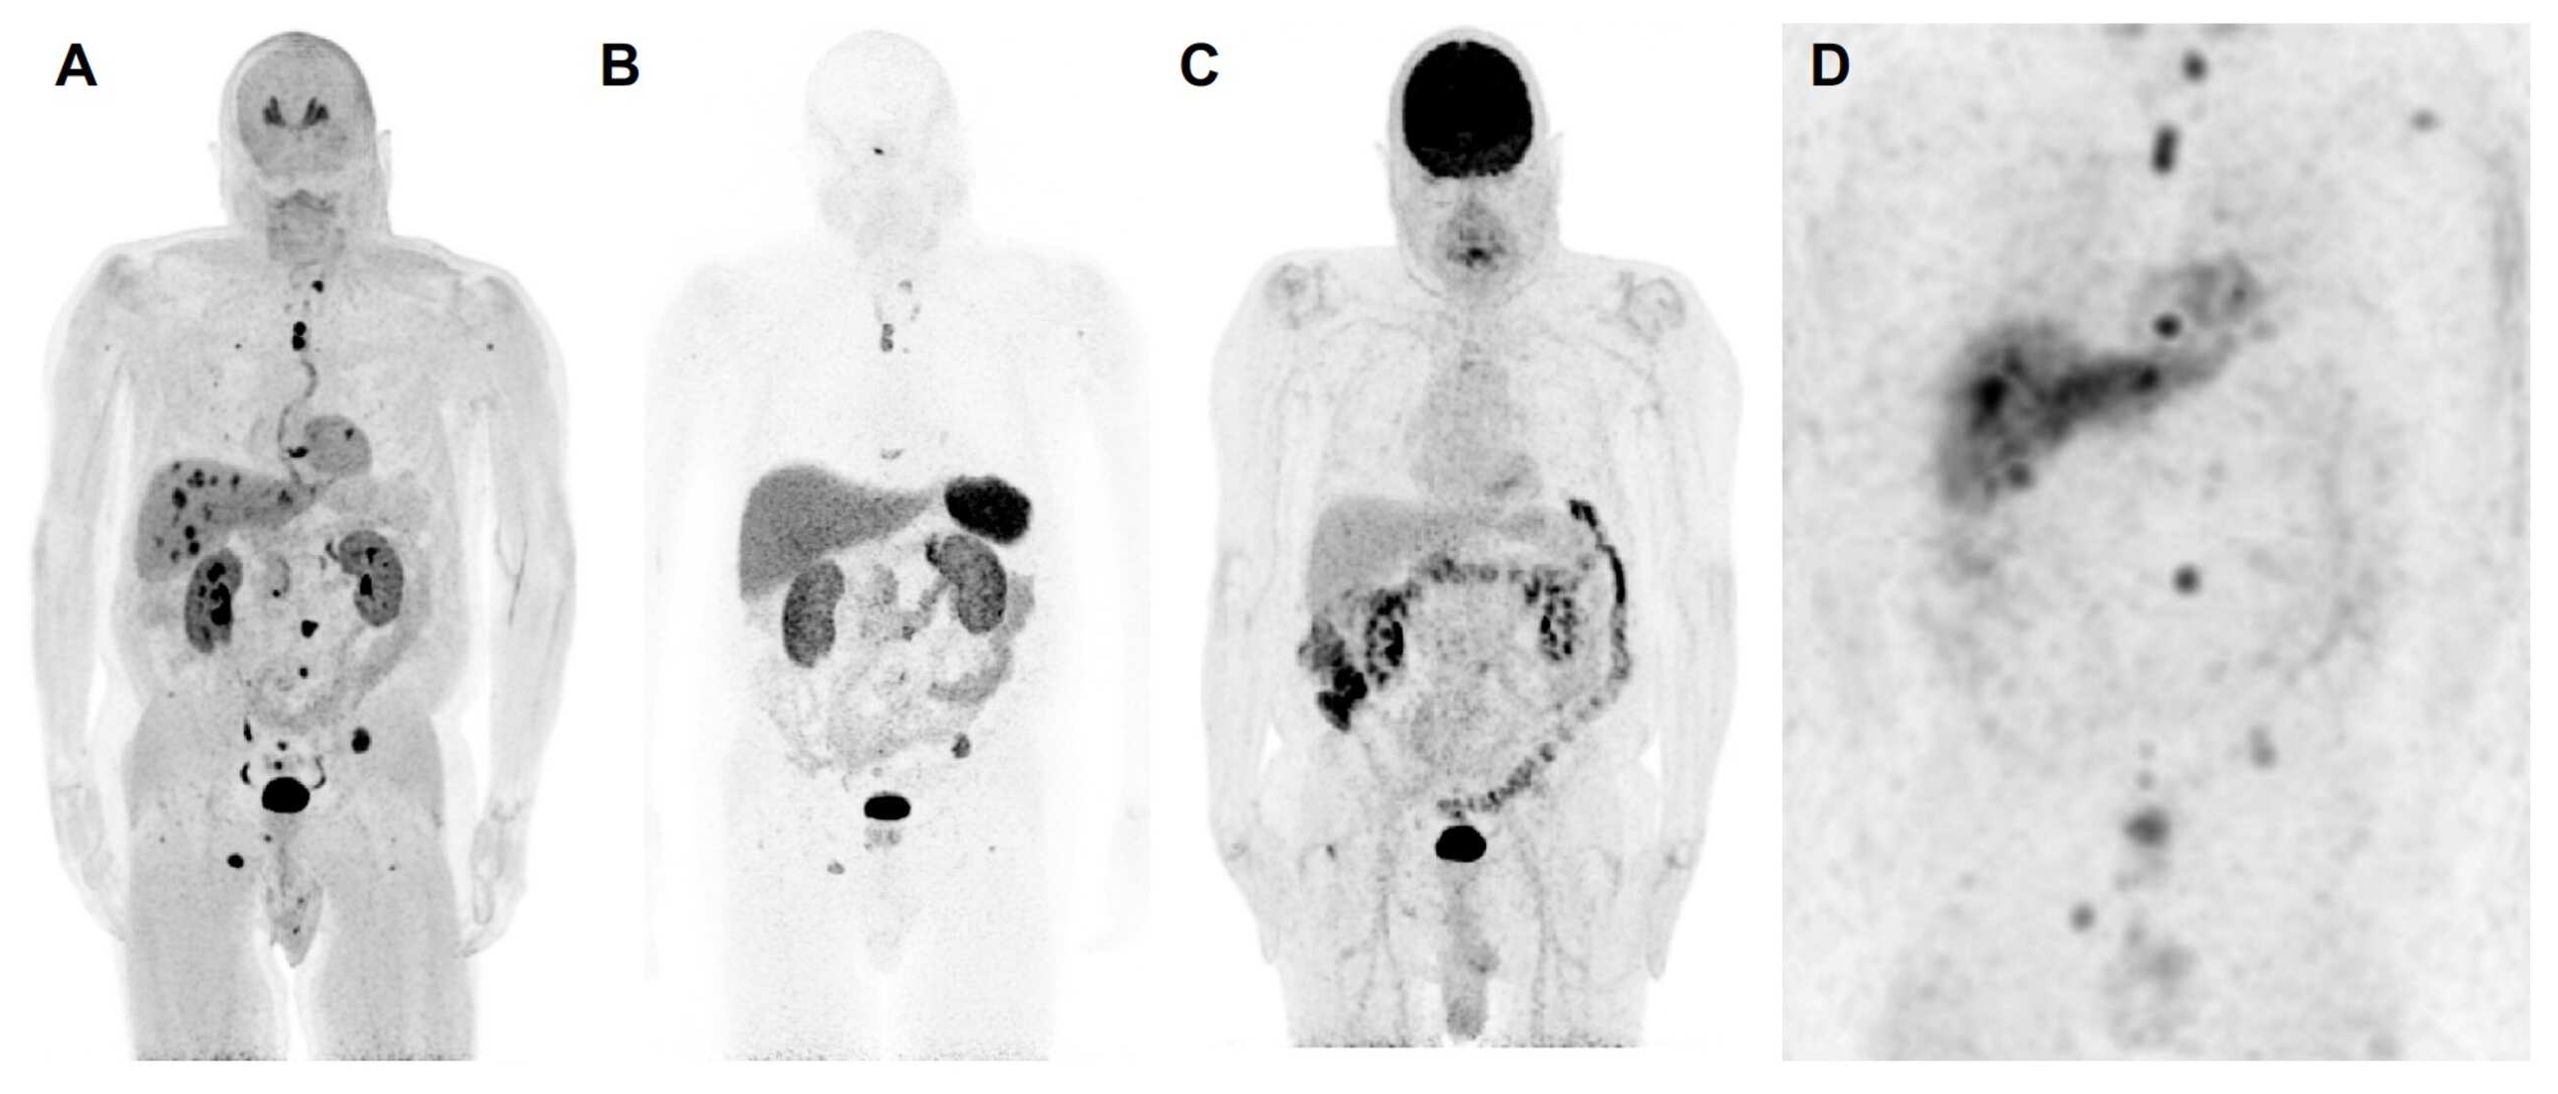

Figure 1. The anterior maximum intensity projection images of 18F-FDOPA positron emission tomography/computed tomography (PET/CT) (A), 68Ga-DOTATATE PET/CT (B), 18F-FDG PET/CT (C), and 123I-MIBG single photon emission computed tomography/computed tomography (SPECT/CT) (D) of a 67-year-old male (patient 3) with a likely oncogenic somatic ATRX variant (c.2018dup, p.Thr674fs) with a history of a previously resected 8.7 cm right pheochromocytoma demonstrates metastatic lesions in lungs, liver, and bones. 18F-FDOPA PET/CT shows superiority in detection of metastatic lesions compared to 68Ga-DOTATATE PET/CT, 18F-FDG PET/CT, and 123I-MIBG SPECT/CT. Liver lesions are detected by 18F-FDOPA PET/CT and 123I-MIBG SPECT/CT and are not seen on 68Ga-DOTATATE PET/CT and 18F-FDG PET/CT. Furthermore, 18F-FDOPA PET/CT detects more bone and lung lesions compared to 68Ga-DOTATATE PET/CT, 18F-FDG PET/CT, and 123I-MIBG SPECT scintigraphy. Based on widespread avidity of metastatic lesions on 123I-MIBG scintigraphy compared to 68Ga-DOTATATE PET/CT, the patient was recommended for high-specific-activity 131I-MIBG (Azedra®) targeted radiotherapy. Additionally, 18F-FDG PET/CT demonstrates diffuse increased uptake in the colon, likely physiologic and not suggestive of malignancy. The 18F-FDA PET/CT, unfortunately, was not performed in this patient. To note, contrast recovery, sensitivity, and spatial resolution of PET/CT imaging is superior to SPECT/CT imaging, and therefore, smaller lesions on PET/CT scans may not be visible on SPECT/CT scans despite adequate uptake.

Functional imaging studies evaluating metastatic disease are summarized in Supplementary Table 4. Of four patients, all (100%) underwent 18F-FDOPA PET (n=1, 25%, patient 1) or PET/CT (n=3, 75%; patients 2–4), and three (75%, patients 2–4) underwent 68Ga-DOTATATE and 18F-FDG PET/CT. Three patients (75%) had 18F-FDA PET (n=1, 33%, patient 1) or PET/CT (n=2, 67%, patients 2 and 4). Finally, two patients had additional 123I-MIBG imaging (50%, patients 2 and 3). 68Ga-DOTATATE PET/CT did not detect liver metastases in patient 3, which were seen on CT, 123I-MIBG scintigraphy, 18F-FDG, and 18F- FDOPA PET/CT.

The total number of lesions identified among all patients was 81. The per-lesion detection rate of 18F-FDOPA PET or PET/CT was 100% (81/81, 95% CI 95.6–100%), which was superior compared to that of 68Ga-DOTATATE PET/CT (82.7% [62/75], 95% CI 72.2–90.4%, p=0.0001), 18F-FDG PET/CT (53.3% [40/75], 95% CI 41.5–65.0%, p=0.0001), and 123I-MIBG scintigraphy (78.9% [30/38], 95% CI 62.7–90.5%, p=0.0005). The difference in per-lesion detection rates between 18F-FDOPA PET/CT and other functional imaging modalities reached statistical significance except for 18F-FDA PET or PET/CT (90% [45/50], 95% CI 78.2–96.7%, p=0.055), which tended towards significance (p=0.055). 18F-FDG PET/CT performed the worst in comparison to all other functional imaging modalities. The per-patient detection rate of all performed functional imaging modalities was 100% (Table 2).

Our small cohort of PCCs with ATRX variants also provides insight on functional imaging modalities in these patients. 18F-FDOPA PET/CT was shown to be superior to all other functional imaging modalities, with 100% lesion detection in each patient as compared to the reference standard. 18F-FDG PET/CT performed the worst in these patients, with a per-lesion detection of only 53.3%. Thus, 18F-FDOPA PET/CT seems to be the imaging modality of choice for these patients, similar to patients having pathogenic variants in cluster 1b or 2 genes or those with sporadic PCCs (31–35). It is important to note that while patient 2, with a pathogenic VHL variant, already falls into cluster 1b, associated with preferred 18F-FDOPA PET/CT imaging, patient 4, with an FH variant (cluster 1a) may have been appropriately imaged with 68Ga-DOTATATE PET/CT or 18F-FDOPA PET/CT given prior reports (36, 37). These data suggest that the presence of ATRX variants favors 18F-FDOPA PET/CT as the imaging modality of choice.